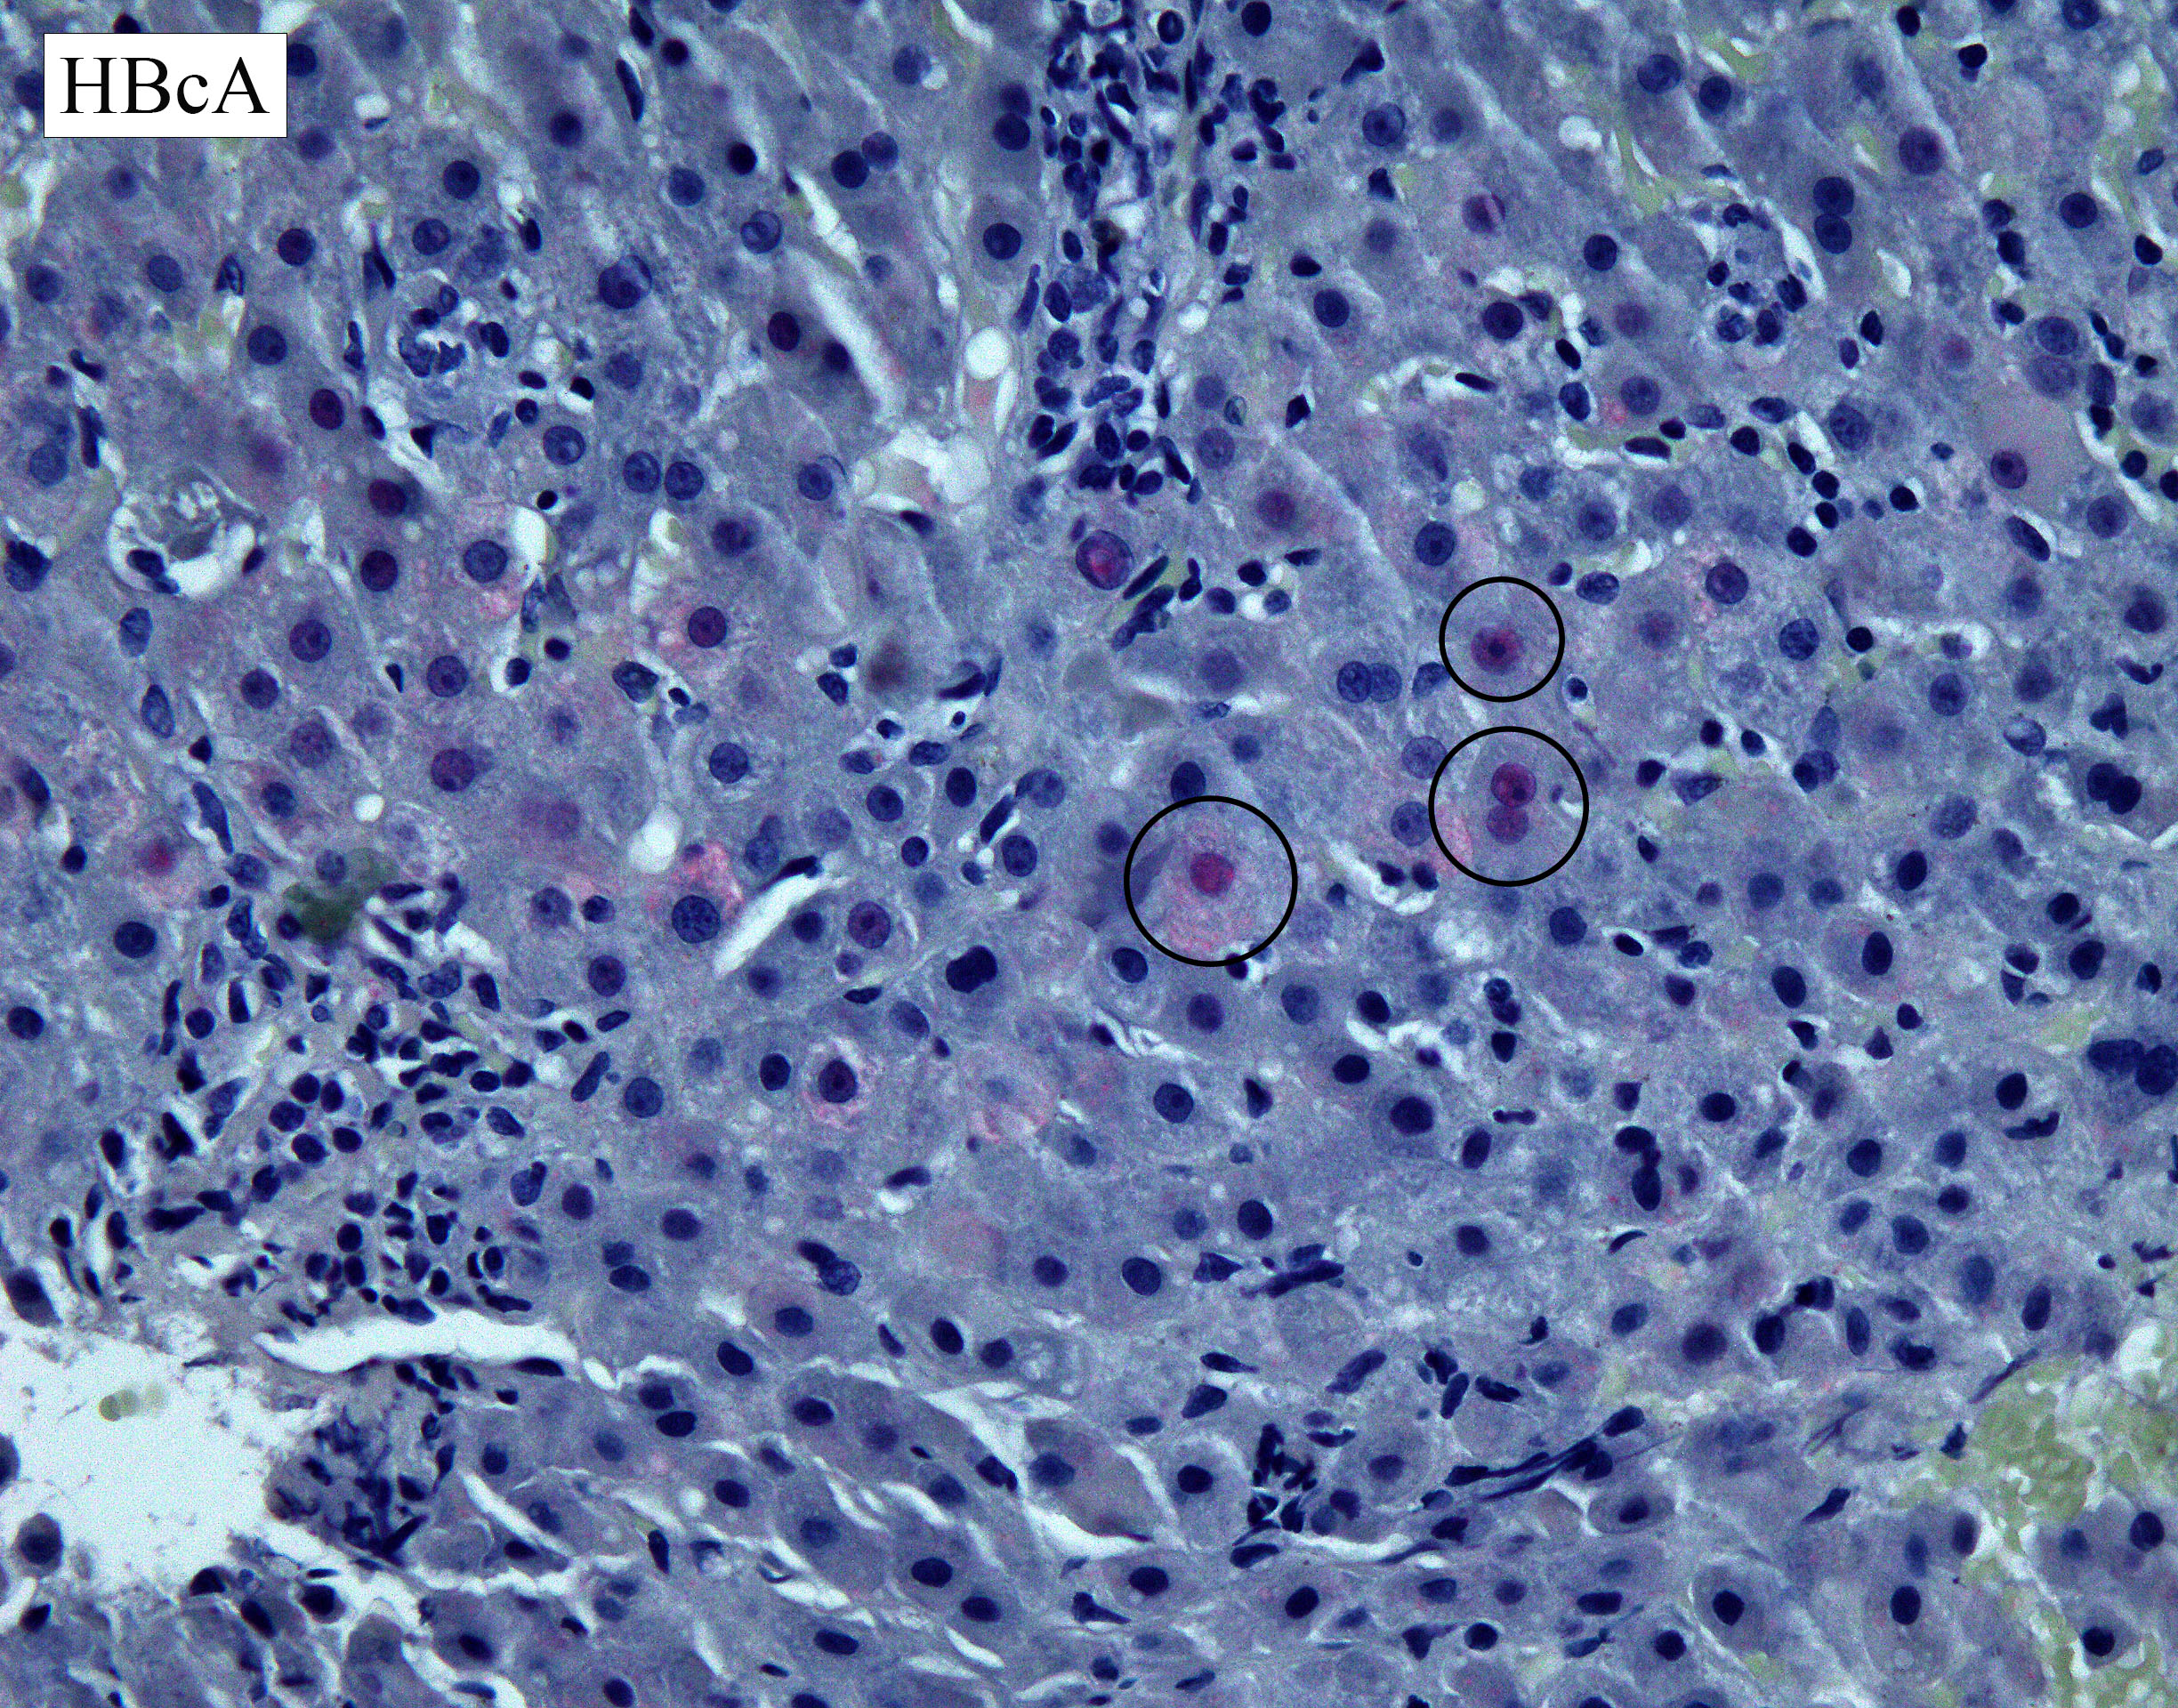

Given the clinical history, hepatitis B core (HBcA) and surface antigen (HBSA) immunostains are performed.  The HBcA stain is positive, showing nuclear and cytoplasmic staining (Figure 4). The HBSA stain is also positive, demonstrating strong cytoplasmic staining (Figure 5).

Figure 4. HBcA immunostain demonstrating nuclear and cytoplasmic positivity (red-pink hue), supporting the diagnosis of hepatitis B.